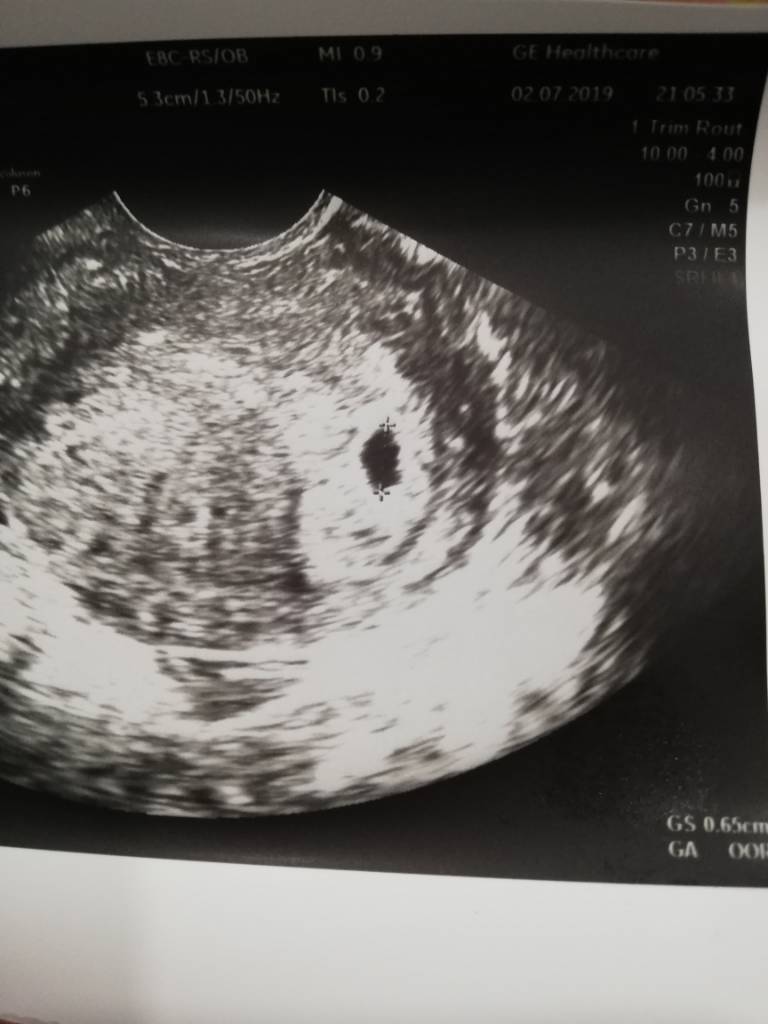

Mam taką samą sytuację, ciąża młodsza więc będę marcowa, sama jestem z marca także mnie to cieszy [emoji7] a to mój pęcherzyk

IMG_20190702_201330.jpeg